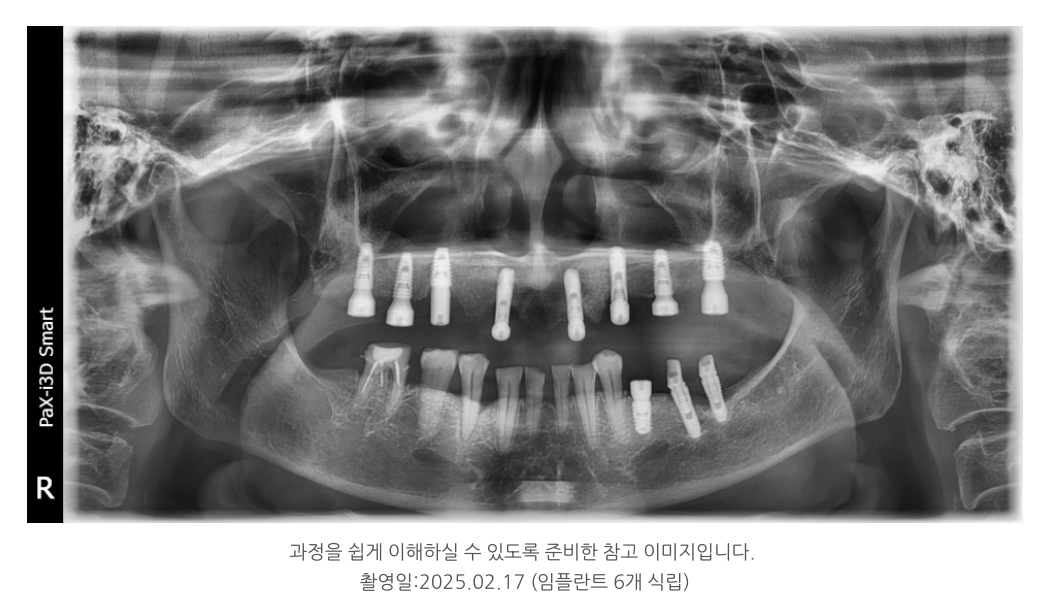

기존 임플란트 중 상태가 양호한 2개는 보존하고,

부족한 부위에는 새로 6개를 심어 총 8개로 구성했습니다.

이로써 힘이 고르게 분산되도록 설계했고,

부족한 뼈에는 뼈이식을 병행해 안정성을 높였습니다.